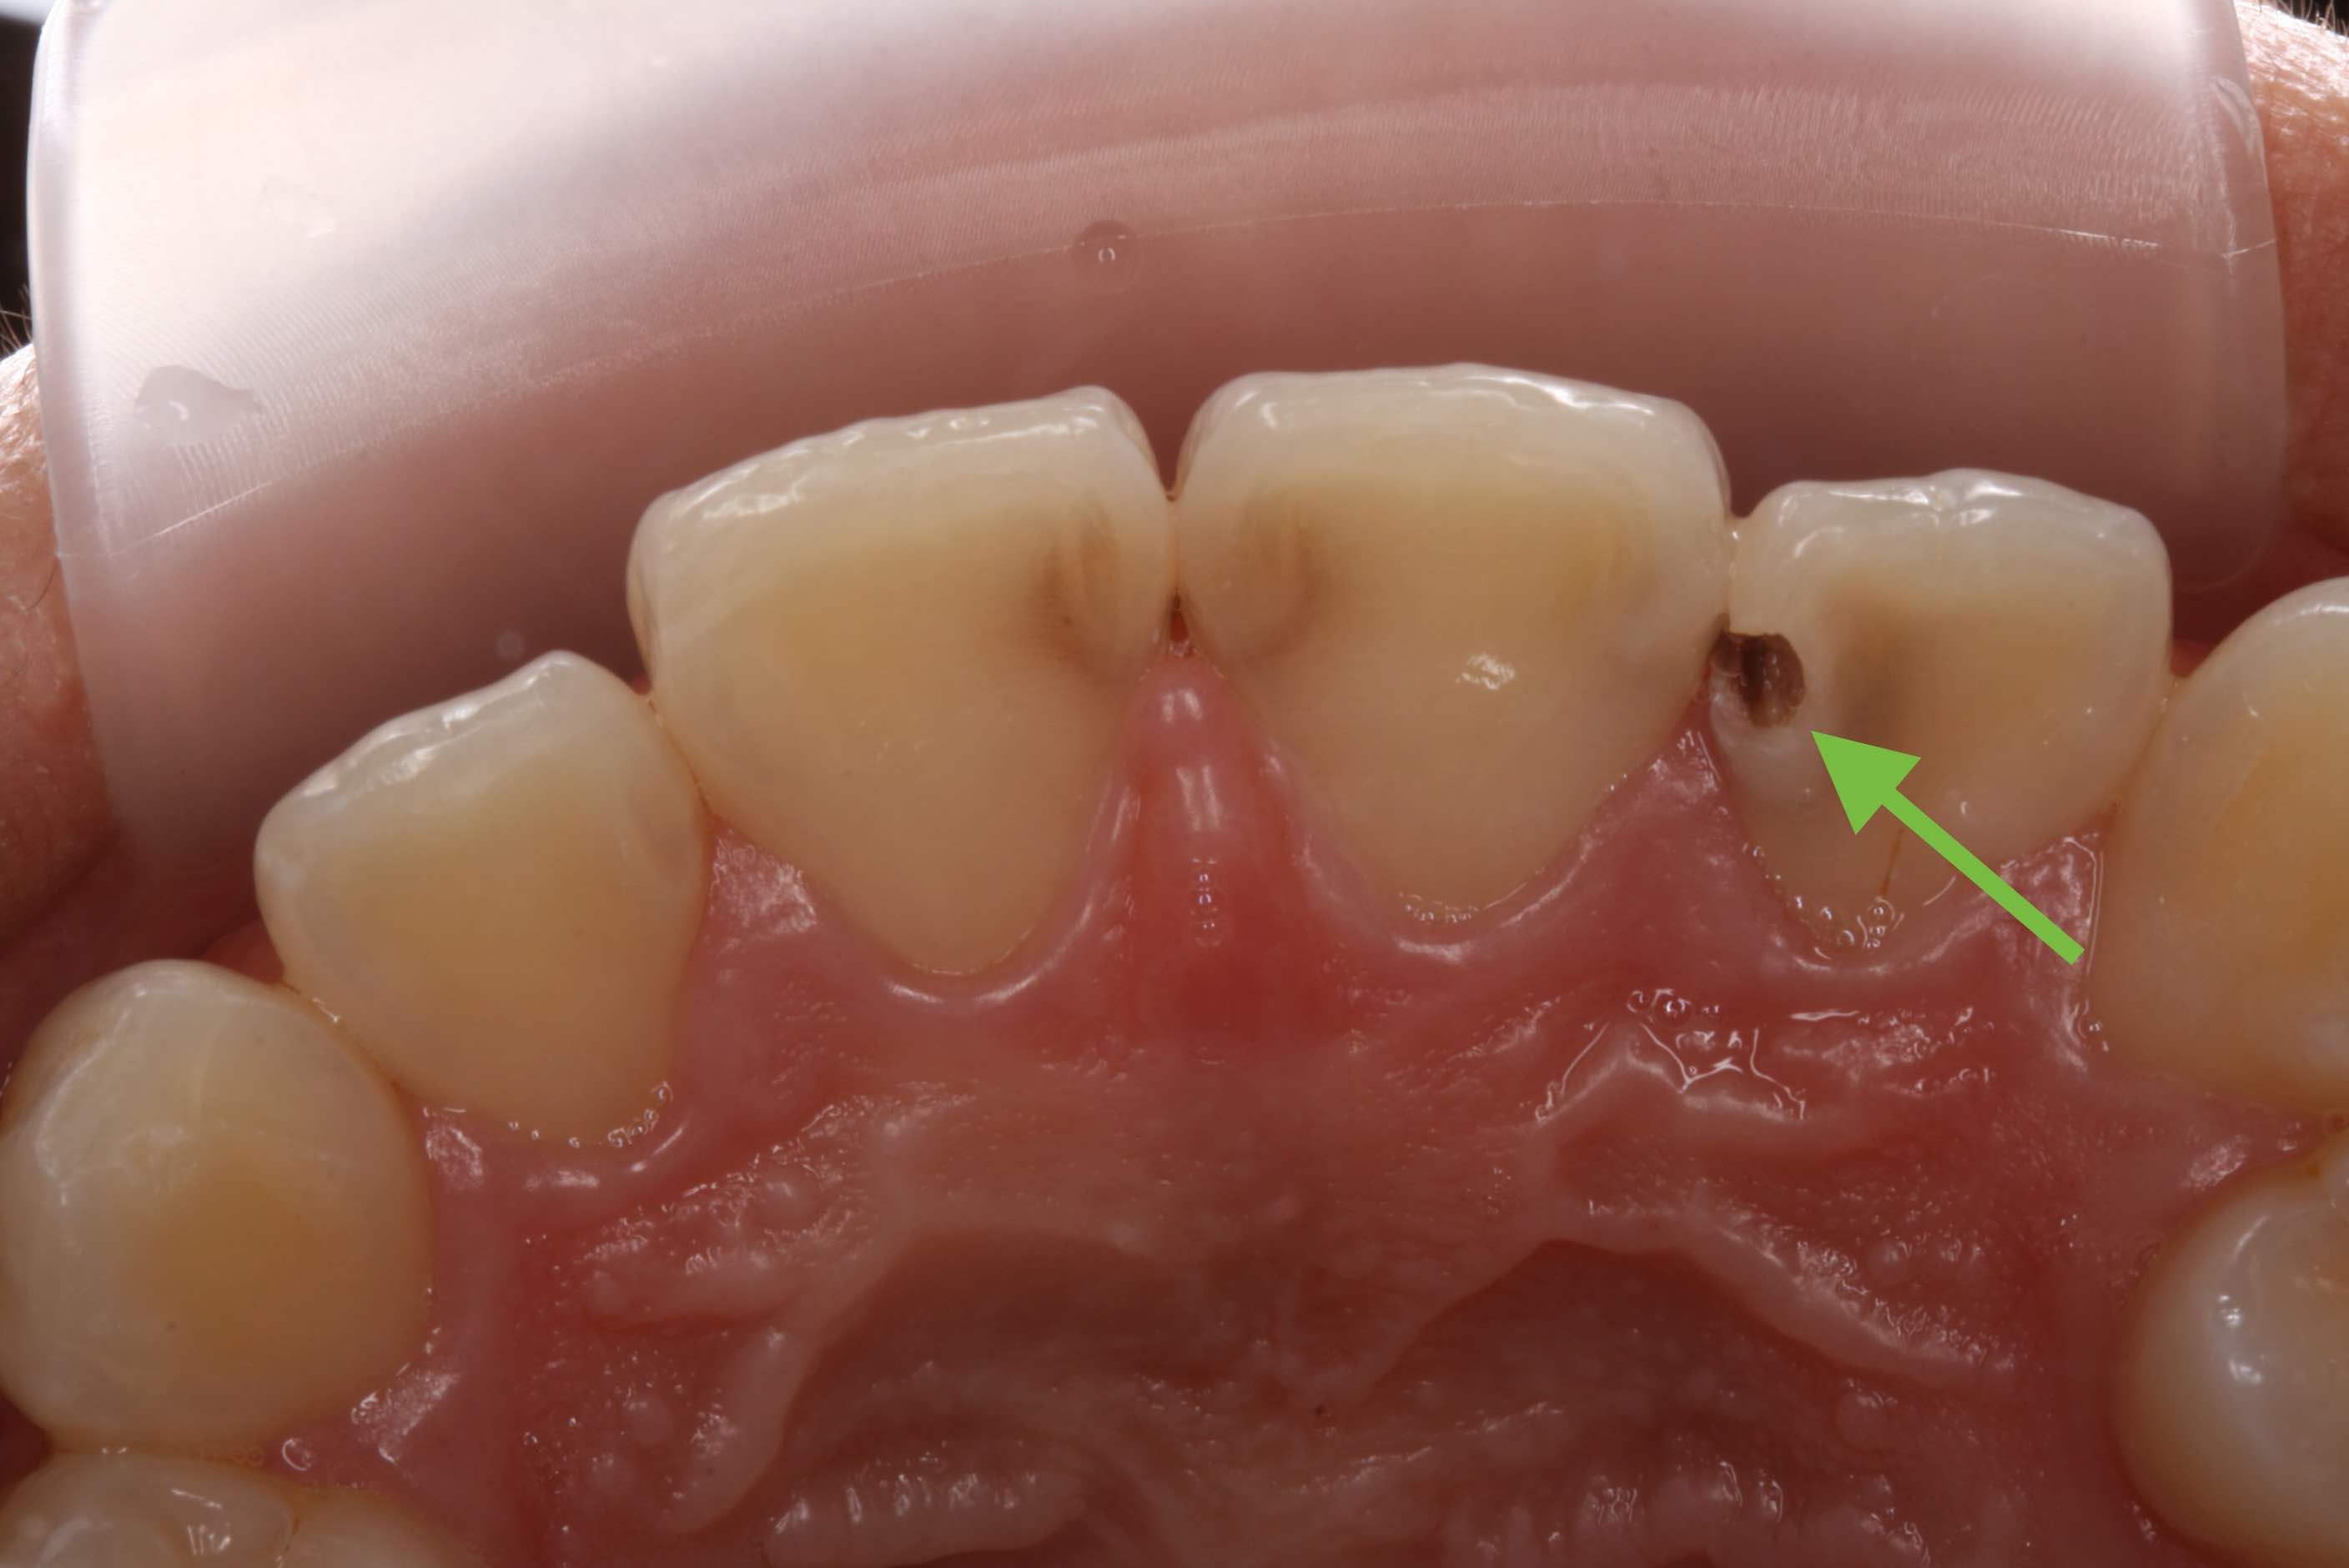

虫歯をきれいに除去したときに、神経が見えたらいつも判断に悩んでしまいます。

神経を取り除く(抜髄)か神経を温存する薬を塗る直接覆髄をするかです。

そこで、意図的に虫歯を少し残して、間接的に神経を温存する薬を塗り、とりあえず歯に詰め物をして終了します。その後、定期的にレントゲンを撮影して、象牙質ができたか確認し、もう一度残してきた虫歯を取り除いて詰め物をします。薬は抗生物質(3MIX)よりもHYカルボテンポラリーソフトの方が学会のお墨付きもあり、予後が良いです。